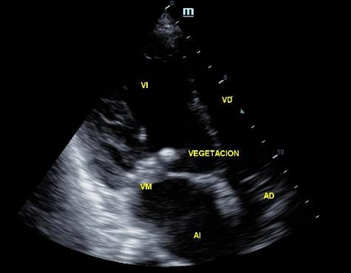

During hospitalization, clinical signs suggestive of infective endocarditis (Janeway lesions) were documented and an echocardiogram was performed, which found vegetations in the anterior mitral leaflet and right coronary leaflet (Figure 2), confirming the suspected diagnosis. Despite pharmacological management, the patient progressed to septic shock with no response to the measures implemented in the intensive care unit and died 48 hours later.

Figure 2 Vegetation in the anterior mitral leaflet.